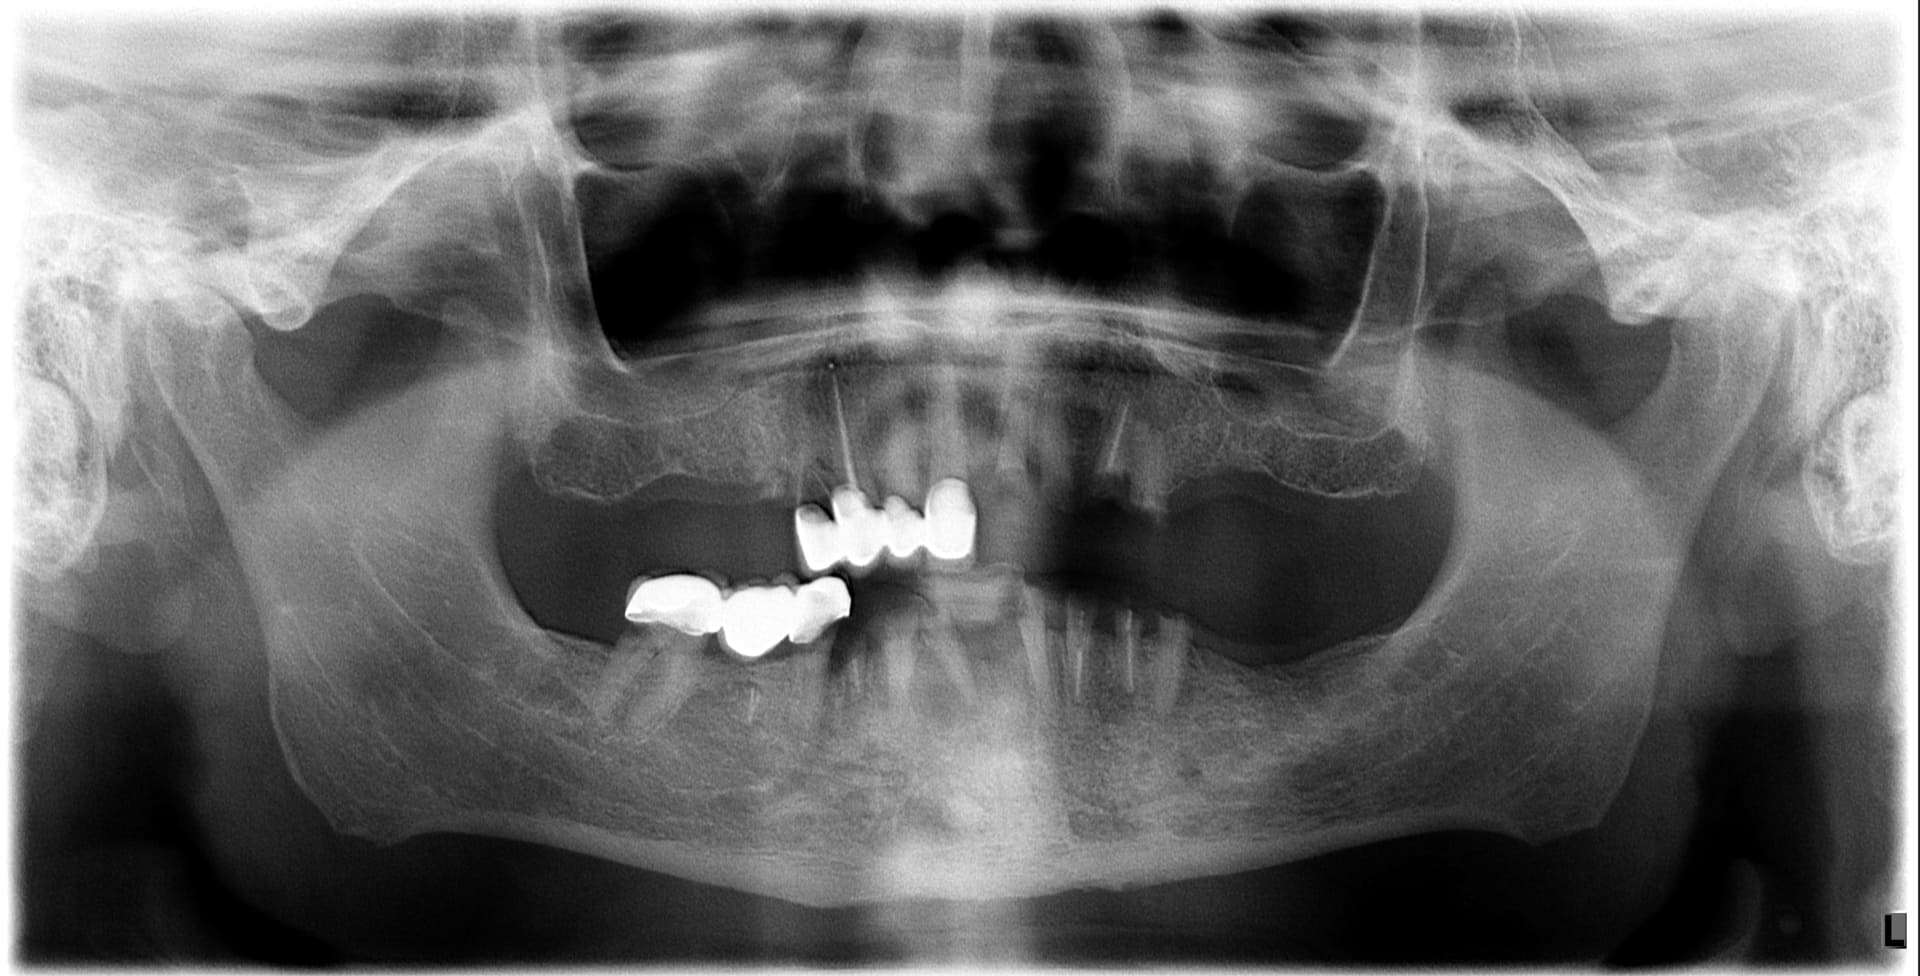

Paziente 2

< Prima